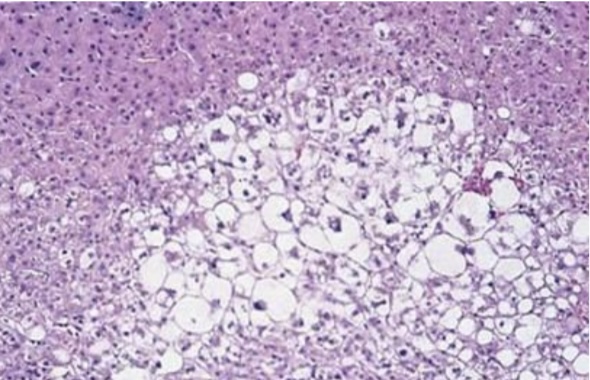

Fat necrosis